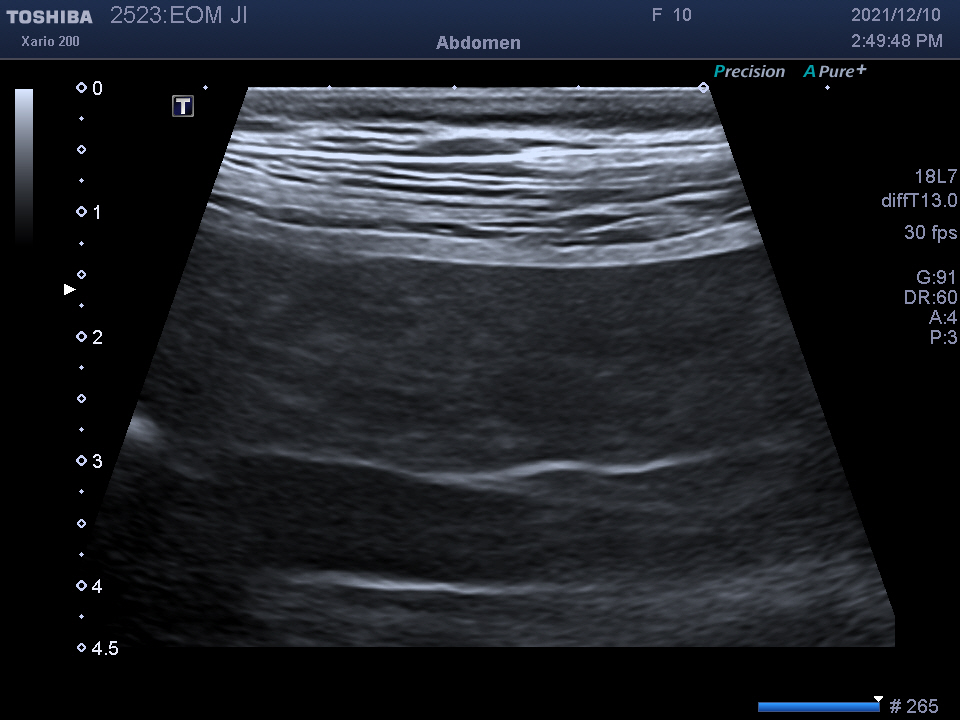

복강 내 장기를 자세히 알 수 있는

복부 초음파 검사를 진행하였습니다.